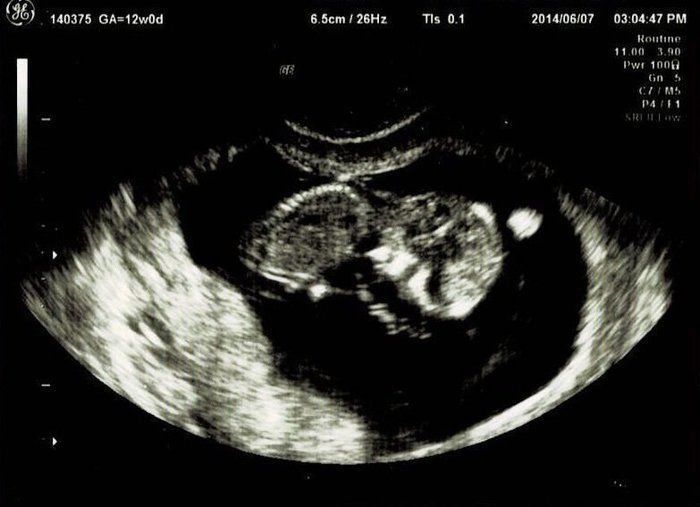

「5回目の体外受精で妊娠」エコー写真で綴る “高齢妊婦が赤ちゃんに出会うまで“の泣き笑い日記 -

不妊治療や2度の流産経験を経て「初めての出産」。日々成長する胎児の記録をエコー画像で振り返る -